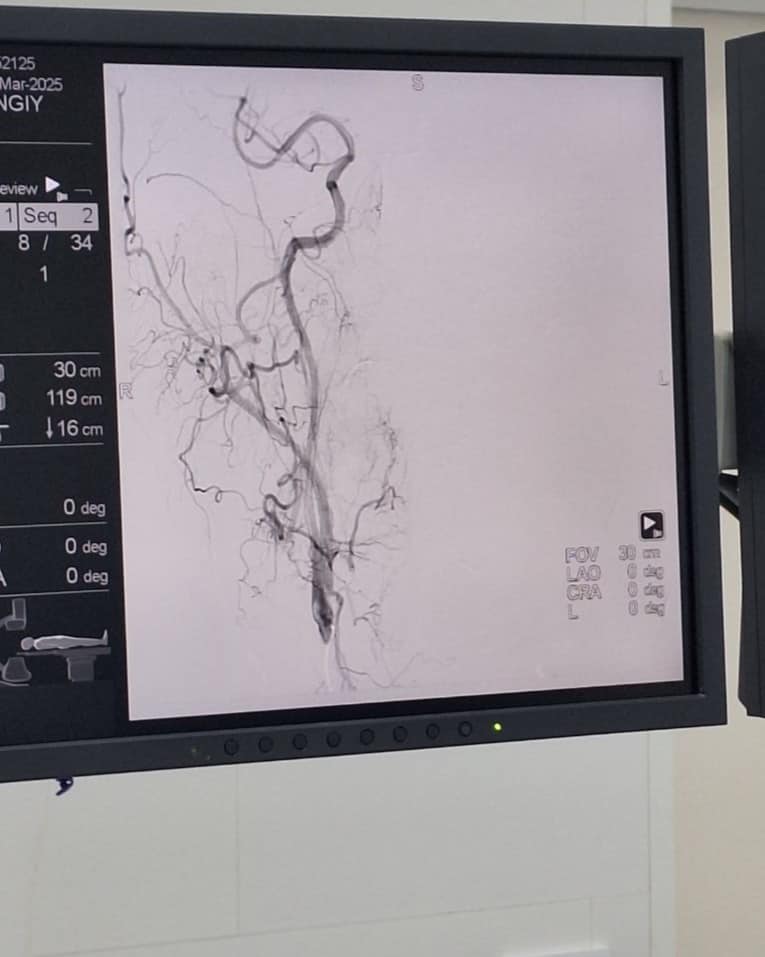

Вчергове у КНП «Нововолинська ЦМЛ» врятували пацієнта з інсультом. Хворому провели видалення тромбу з мозку мініінвазивно, через маленький прокол в паховій ділянці.

Тромбоекстракція – найсучасніший ендоваскулярний метод лікування ішемічного інсульту в гострому періоді. Він полягає у видаленні тромбу з артерій головного мозку з подальшим відновленням кровотоку та запобіганню розвитку ішемічного інсульту в даній ділянці.

Виконується дане ендоваскулярне втручання на ангіографічній системі за допомогою стента-ретрівера – спеціального циліндричного металічного пристрою, який вводиться безпосередньо в тромб, захоплює його і видаляє з закупореної судини.